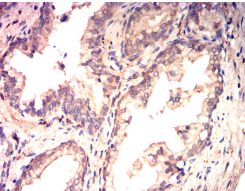

ITGA1 Mouse Monoclonal antibody[5F9H1]

IHC    1/200 - 1/1000